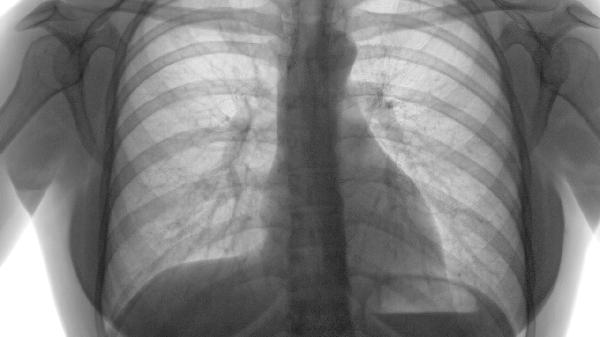

肺病患者睡觉总半夜2、3点醒来,一般暗示这些并发症,要注意了

肺部功能受损时,夜间血氧饱和度会明显下降。凌晨2-3点恰逢人体代谢低谷期,此时身体对缺氧更为敏感。大脑感知到氧气不足,会通过"强制开机"的方式促使你改变呼吸模式,这种保护机制反而打断了睡眠周期。

慢性阻塞性肺疾病患者常面临二氧化碳排不出去的困扰。躺平姿势使膈肌活动受限,积聚的二氧化碳刺激呼吸中枢,让你在深度睡眠期突然惊醒。这种情况往往伴随晨起头痛、白天嗜睡等连锁反应。